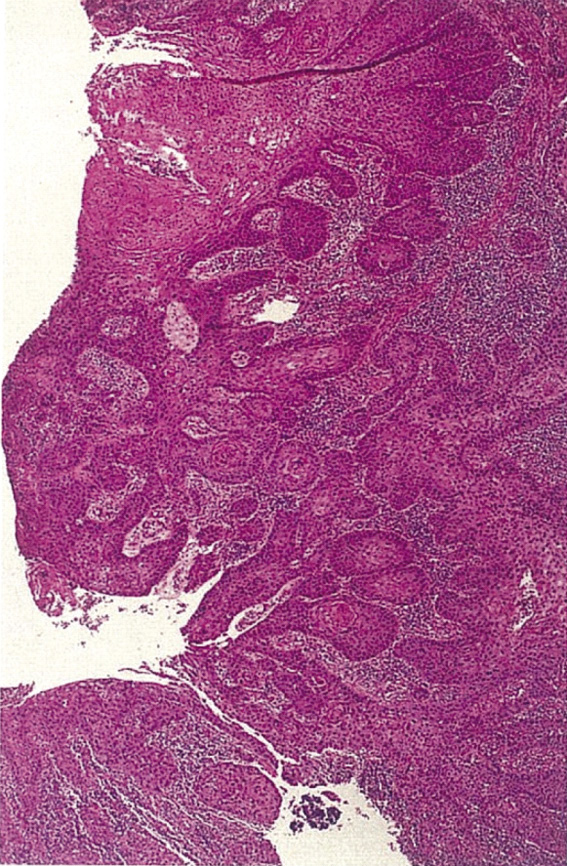

Figura 2. Reperto istologico di carcinoma squamoso con pattern di crescita endofitica infiltrativa, cheratinizzante, da moderatamente a scarsamente differenziato

L’esame istopatologico del pene distale evidenzia un carcinoma squamoso con pattern di crescita endofitica infiltrativa, cheratinizzante, da moderatamente a scarsamente differenziato. La neoplasia infiltra il corpo spongioso, i corpi cavernosi e l’uretra; si associa, inoltre, l’invasione neoplastica perineurale. Il moncone uretrale prossimale risulta invece esente da infiltrazione neoplastica (pT3) (Figura 2).